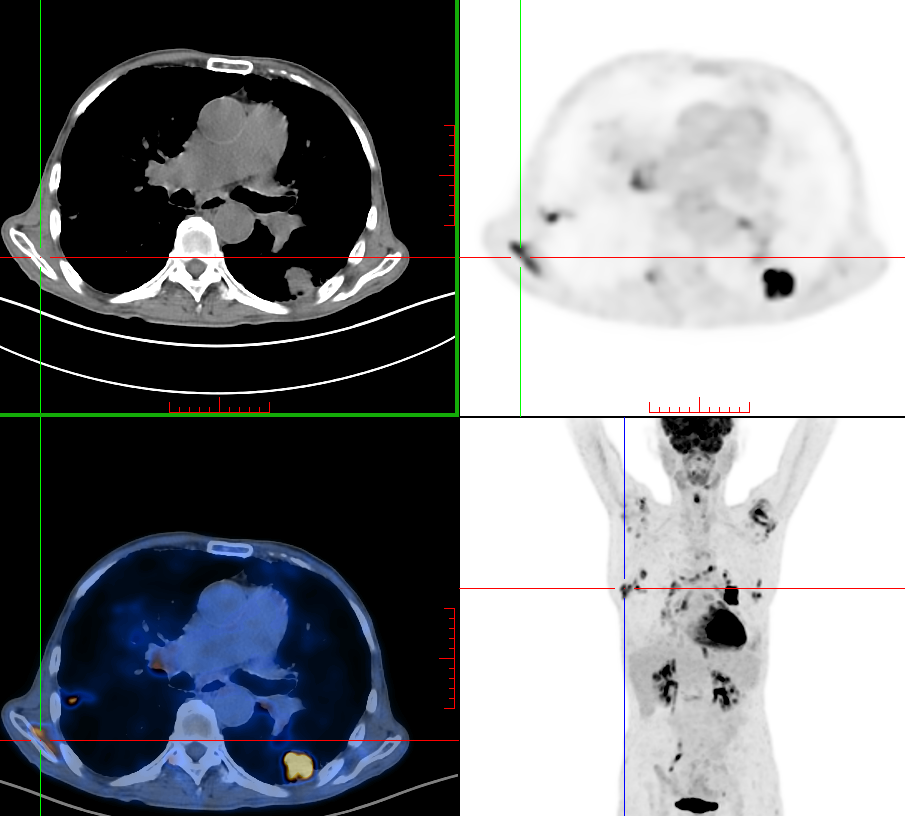

上圖為PET/CT顯像

集功能代謝顯像與解剖顯像的優(yōu)勢于一身,為臨床提供早期診斷、分期、療效評估、預(yù)后評價等一站式服務(wù)。其可以對腫瘤性疾病進行早期診斷、鑒別診斷,指導(dǎo)治療方案制定及進行腫瘤治療后的療效評價;又可以對冠心病進行評價,它是判斷心肌梗塞部位心肌是否存活的金標準,為冠心病的治療、療效評估和預(yù)后評價提供準確的依據(jù);還可以對神經(jīng)及精神系統(tǒng)疾病如腦缺血性疾病、癲癇、早老性癡呆、精神性疾病進行早期診斷,以及對正常腦功能評價等。

在《關(guān)于唐醫(yī)生的一切》劇中所說的放射性核素全身掃描其實是指:PET/CT腫瘤顯像或者是SPECT/CT全身骨顯像,二者均可一站式檢出全身有無轉(zhuǎn)移性病灶,只是SPECT/CT全身骨顯像只能檢出骨骼轉(zhuǎn)移灶。